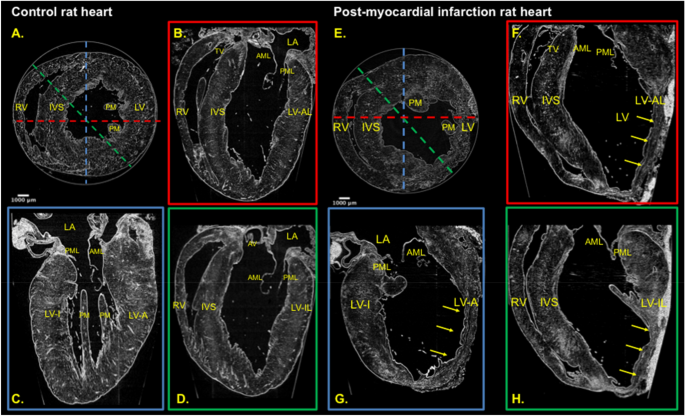

Assessment of viable versus scarred heart muscle

- To differentiate ischemic vs. non-ischemic cardiomyopathy